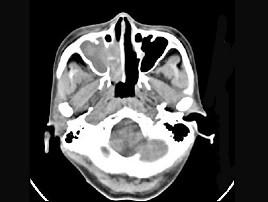

女性,53岁,右侧鼻腔流血近一年,近来头痛,行CT检查如图所示,请选择正确的答案 ( )

• A.鼻腔内血管瘤

• B.鼻腔内息肉

• C.鼻腔癌

• D.鼻腔炎性假瘤

• E.副鼻窦炎

答案: C